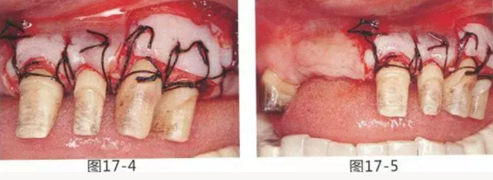

圖17-4 左上1,2進行齦瓣根尖側(cè)轉(zhuǎn)移,左上3,4進行游離牙齦移植,在去除牙周袋的同時獲取附著齦。

圖17-5 牙周治療完成后的正面照。左上3,4部位處游離齦移植片的上端通過骨膜縫合固定在頰側(cè)嵴頂部。這樣可以使其愈合效果與齦瓣根尖側(cè)轉(zhuǎn)移相同。

圖17-6 牙周外科處理完成6個月后,取模前狀態(tài)。獲得了足夠附著齦,右側(cè)牙齦也無段差。

圖17-7 佩戴最終修復體時的正面照。通過臨時修復體對美觀性,機能性,清潔性進行了充分確認,轉(zhuǎn)為最終修復。